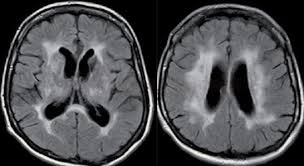

Name the condition

Porencephaly